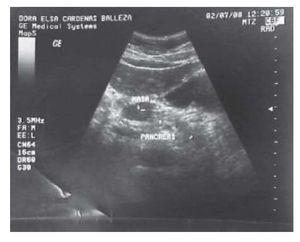

Paciente femenino de 42 años, sin antecedentes de consideración para el padecimiento que inició tres años antes con dolor en el epigastrio de tipo ardoroso, que se irradiaba de modo ocasional al hipocondrio derecho y espalda, acompañado de náusea y vómito. Los síntomas se acentuaron en forma progresiva, con aparición concurrente de vómito posprandial, que propició intolerancia a los alimentos, y se asoció con esteatorrea. Se sometió a tratamiento durante más de dos años con bloqueadores de los receptores H2 de la histamina (BH2). Se detectó litiasis vesicular, razón por la cual se la programó para colecistectomía laparoscópica, pero el resultado no fue satisfactorio. Continuó con pérdida de peso involuntaria y significativa mayor de 10 kg en el último año. Presentó hematemesis y ello obligó a efectuarle una esofagogastroduodenoscopia que demostró esofagitis y gastritis graves. Se inició tratamiento con bloqueadores de la bomba de protones (IBP) a dosis altas, con mejoría parcial. Se realizó una ecografía abdominal que delineó la presencia de una masa homogénea en la cabeza del páncreas de 1.95 x 2.24 cm (Figura 1). Sin embargo, la tomografía computarizada de abdomen no confirmó ese hallazgo. Se decidió suspender la administración de IBP para cuantificar la gastrina sérica, que se encontró en concentraciones de 17 251 μg/L (normal, 110 μg/L), por lo que se estableció el diagnóstico de gastrinoma. Se propuso realizar una laparotomía exploradora con ultrasonografía transoperatoria, que permitió localizar la tumoración en la cabeza del páncreas, que se logró enuclear (Figuras 2 y 3). También se reconocieron tres lesiones metastásicas en el lóbulo hepático izquierdo (Figura 4).

Figura 1. Ultrasonido abdominal que muestra una imagen nodular en la cabeza del páncreas, homogénea e hipoecoica, con diámetro de 1.95 x 2.24 cm.

Las manifestaciones clínicas principales fueron dolor abdominal y diarrea, que se presentan en más de 50% de los casos.9 Tan sólo la diarrea aparece en más de 70% de los casos.9 Por lo general, estos pacientes refieren síntomas de enfermedad acidopéptica, que suele tratarse de forma médica durante un periodo largo de tiempo, sin sospecha de gastrinoma. Este último debe investigarse ante la presencia de úlceras pépticas en pacientes jóvenes, enfermedad acidopéptica agresiva o resistente al tratamiento, úlceras pépticas en localizaciones poco habituales (tercera o cuarta porciones del duodeno) o sujetos con sospecha de neoplasia endocrina múltiple por antecedentes personales o familiares. Los estudios de imagen que ayudan a establecer el diagnóstico presentan una sensibilidad variable; el ultrasonido endoscópico es el estudio de mayor sensibilidad, pero su disponibilidad es limitada. Sin embargo, el ultrasonido abdominal puede detectar los tumores hasta en 50% de los casos y fue el método que permitió reconocer la tumoración en la cabeza del páncreas de esta paciente. En este caso, la tomografía computarizada no pudo confirmar el hallazgo, pero las concentraciones tan elevadas de gastrina sérica (17 251 μg/L) corroboraron la sospecha clínica. El ultrasonido transoperatorio fue una herramienta muy útil en la localización de la neoformación. Cerca de 90% de estos tumores se localiza en el triángulo del gastrinoma (límite superior, en la unión entre los conductos cístico y hepático común; límite inferior, en la unión entre la segunda y tercera porciones del duodeno, y límite medial, en la unión entre cuello y cuerpo del páncreas).10 Más de 50% se aloja en el duodeno en el siguiente orden de frecuencia y ubicación anatómica: primera porción, 56%; segunda porción, 32%; tercera porción, 6%, y cuarta porción, 6%. En el páncreas, la distribución es de 2:1 (cabeza/cola), 10% en ambos sitios y en 24% no se identifica. Es esencial realizar estudios de imagen minuciosos para localizar la extensión del tumor. El ultrasonido es capaz de detectar entre 20% y 50% de los tumores, la tomografía axial alrededor de 40%, la resonancia magnética del 20% y el ultrasonido endoscópico entre 65% y 85%, por lo cual este último se recomienda como primera opción.1,9,11 El gastrinoma puede estadificarse de acuerdo con los criterios TNM (estadios 0-III) o por el tamaño del tumor; esto representa notables diferencias en las curvas de supervivencia.12 Alrededor del 33% de los pacientes presenta metástasis hepáticas, y en menos del 15% de estos casos es posible la resección quirúrgica.